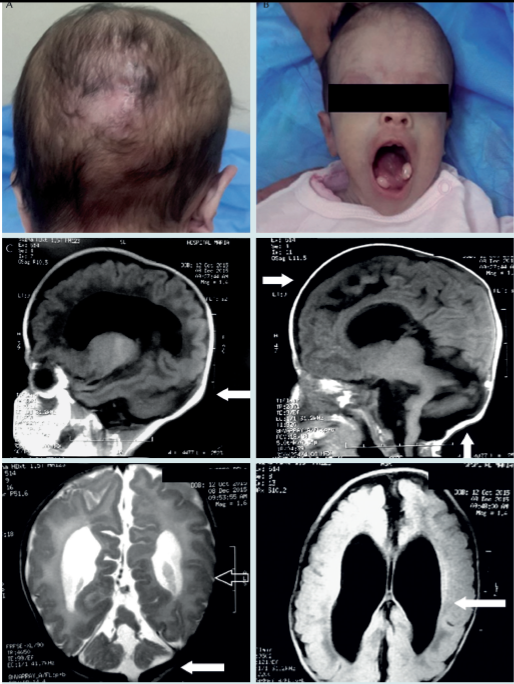

Niña de 11 meses de vida, hondureña, producto de la primera gesta de madre de 19 y padre de 37 años, no consanguíneos según refirieron. Durante los controles prenatales se detectaron oligohidramnios y defectos congénitos múltiples, sin reportar MGS. Parto normal, a término de 37 semanas de gestación, con Apgar de 6/7 y con datos de hipoxia cerebral, reflejo de moro incompleto. Peso al nacer de 2.7 kg, perímetro cefálico de 31 cm, por debajo del percentil 3 según tablas del CDC, cráneo asimétrico con frente amplia y prominente, defecto óseo y masa que protruye en la región occipital con dimensiones de 4.5 4.5 cm correspondiente a meningoencefalocele occipital, al que se le practicó exéresis a las 72 horas de vida (Figura 1A); también tenía dos protuberancias sublinguales, una lateral derecha y otra lateral izquierda, a las que se les realizó resección quirúrgica resultando, en estudio histopatológico, hamartoma lingual bilateral (Figura 1B). Ojo derecho con fisura palpebral que permanecía cerrada y fisura palpebral izquierda pequeña, ambos globos oculares de apariencia normal, paladar íntegro, cuello corto, abdomen con masas lobuladas en ambos flancos, genitales femeninos sin alteraciones evidentes, extremidades con polidactilia postaxial en manos y pies (Figura 2).

Figura 1 A) Cicatriz secundaria a exéresis de meningoencefalocele. B) Lengua con quistes, hamartoma bilateral y perímetro cefálico de 36 cm a los 4 meses de edad. C) Resonancia magnética, las flechas indican: área de secuelas de exéresis de meningoencefalocele occipital, dilatación de ventrículos laterales, hipoplasia del cuerpo calloso, hipotrofia en hemisferios.

La tomografía cerebral simple posterior a cirugía reveló dilatación de los ventrículos laterales, principalmente de los cuernos anteriores, disminución del volumen de los hemisferios cerebrales con defecto en el parénquima de la región occipital secundario al meningoencefalocele, hipotrofia del cerebelo, disgenesia del cuerpo calloso y de los ganglios basales. La resonancia magnética de control (Figura 1C) mostró dilatación severa de los ventrículos laterales y el tercer ventrículo como compensación a la disminución de volumen de los hemisferios cerebrales, con moderado ensanchamiento del espacio subaracnoideo parietal bilateral; hipoplasia del cuerpo calloso, signos de atrofia córtico-subcortical moderada generalizada; en fosa posterior adelgazamiento del tallo cerebral con ensanchamiento del IV ventrículo y cambios de hipotrofia de los hemisferios cerebelosos relacionados con meningoencefalocele ya reparado, también se apreciaba lisencefalia focal en hemisferio occipital izquierdo.